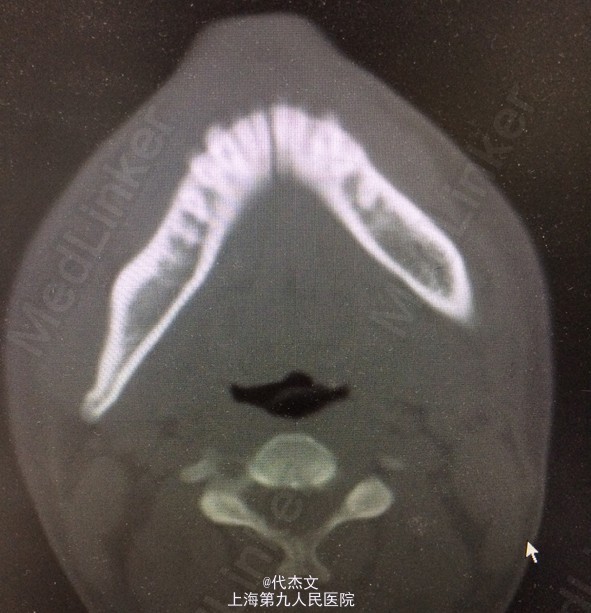

颏部皮肤软组织裂伤,长约5cm,创缘尚齐,深达骨面,渗血。张口度2cm,下颌骨异常动度,CT示下颌颏部骨折;

诊断:面部裂伤,下颌骨骨折 处置:请神外,骨科等相关科室会诊;完善检查,和患者家属交代病情,知情同意下行颏部软组织清除术+颏部骨折切开复位内固定术,术后收入病房,TAT,抗炎消肿治疗,密切观察病情变化